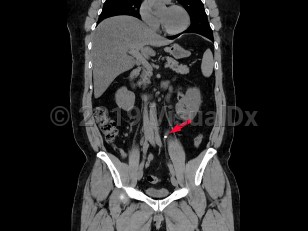

Ureteral calculus

While many stones located within the renal pelvis are discovered incidentally on radiographic or sonographic imaging, most stones that have passed into the ureter and are of significant size cause renal colic. Renal colic is sudden-onset flank pain radiating to the groin, accompanied by nausea and vomiting. This colicky pain typically waxes over the course of 15-30 minutes and becomes steady, unrelenting, and unbearable. Patients may experience worsening paroxysms of pain lasting 20-60 minutes as the stone courses downward through the ureter and as the ureter spasms.

If the stone's descent is arrested at the ureterovesical junction, patients may experience urinary frequency, dysuria, and urgency and are predisposed to the development of urinary tract infections both from the stone forming as a nidus for bacterial growth and from the mechanical urothelial trauma caused by the stone's movement. Most individuals with nephrolithiasis will also develop hematuria, particularly when passing a stone.

Pain from nephrolithiasis is thought to primarily be the result of renal capsular distention and varies depending on the location of the stone and the degree of obstruction caused by the stone. Stones that occlude the upper ureter or ureteropelvic junction invariably cause significant flank pain that is accompanied by severe costovertebral angle tenderness to palpation. As the innervation of the testicle is shared with the kidney, patients often describe radiation to the testicles or labia. When stones pass into the bladder, patients usually experience swift resolution of their pain.